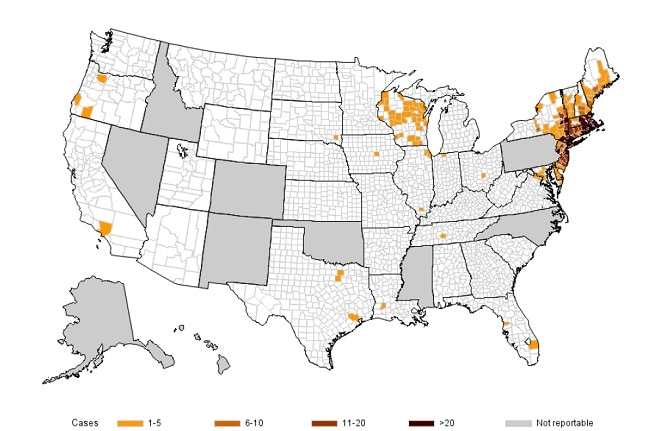

This parasite that causes bladder granulomas and hematuria, while present in Egypt, has a much wider distribution as shown below:

What is Schistosoma haematobium?

These bacteria are spread to people primarily through the bite of infected ticks including the lone star tick. On test questions, it tends to occur in the Ozarks region between AR and MO. Geographical distribution is shown below:

What is Ehrlichia?

(E. chaffeensis, E. ewingii, or E. muris eauclairensis)